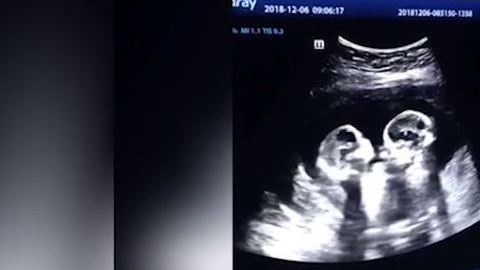

La pelea de unas gemelas dentro del útero de su madre durante una ultrasonido que se hizo viral

Las gemelas parecieran darse unos cuantos golpes.

En redes sociales se ha viralizado un video de un ultrasonido que se realizó una embaraza en donde se aprecia que está en la dulce espera no solo de uno sino de dos bebés. En próximas semanas, la mujer dará a luz a unas gemelas idénticas.

En el ultrasonido se puede ver el momento exacto en el que estas gemelas pareciera que estuvieran peleando entre ellas, pues hacen movimientos como si se patearan o golpearan mutuamente con sus manos.

Rápidamente, varios medios locales de China, en donde se realizó este ultrasonido, divulgaron las imágenes, las cuales ya le han dado la vuelta al mundo.